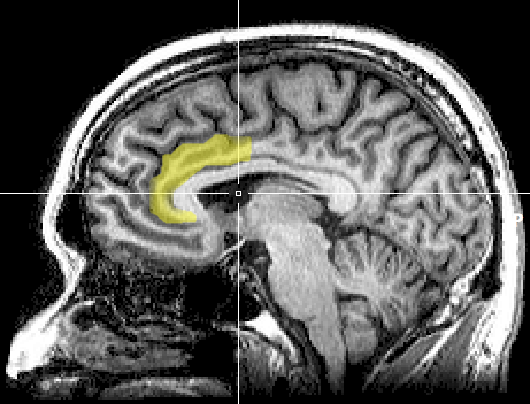

In 2012, researchers at the Yale School of Medicine discovered that the two parts of your brain associated with conflict and pain—the anterior cingulate cortex and insula—overreact whenever you try to let go of possessions that you’re emotionally connected to. [1]